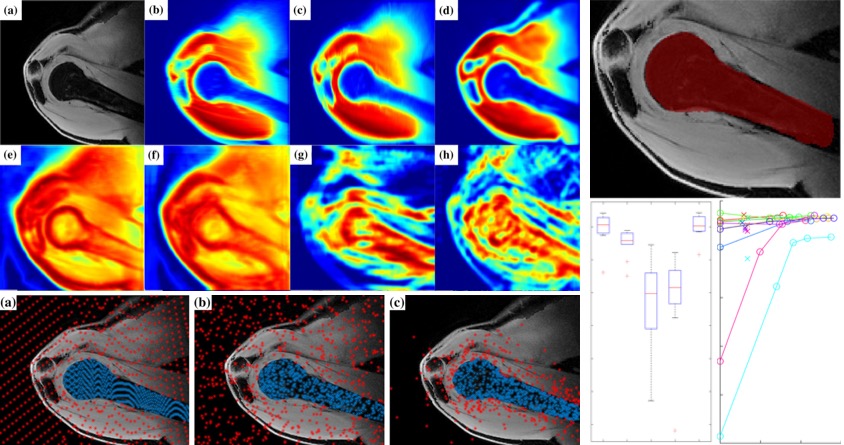

[2022] Fabien Péan, Philippe Favre, and Orcun Goksel:

"Computational Analysis of Subscapularis Tears and Pectoralis Major Transfers on Muscular Activity",

Clinical Biomechanics 92(105541), Feb 2022.

[2022] Fabien Péan, Philippe Favre, and Orcun Goksel:

"Computational Analysis of Subscapularis Tears and Pectoralis Major Transfers on Muscular Activity",

Clinical Biomechanics 92(105541), Feb 2022.

[2021] Fabien Péan, Philippe Favre, and Orcun Goksel:

"Influence of Rotator Cuff Integrity on Loading and Kinematics Before and After Reverse Shoulder Arthroplasty",

Journal of Biomechanics 129(110778), 2021.

[2021] Fabien Péan, Philippe Favre, and Orcun Goksel:

"Influence of Rotator Cuff Integrity on Loading and Kinematics Before and After Reverse Shoulder Arthroplasty",

Journal of Biomechanics 129(110778), 2021.

[2019] Fabien Pean, Christine Tanner, Christian Gerber, Philipp Fuernstahl, and Orcun Goksel:

"A comprehensive and volumetric musculoskeletal model for the dynamic simulation of the shoulder function",

Computer Methods in Biomechanics and Biomedical Engineering (CMBBE) 22(7):740-751, Apr 2019.

[2019] Fabien Pean, Christine Tanner, Christian Gerber, Philipp Fuernstahl, and Orcun Goksel:

"A comprehensive and volumetric musculoskeletal model for the dynamic simulation of the shoulder function",

Computer Methods in Biomechanics and Biomedical Engineering (CMBBE) 22(7):740-751, Apr 2019.

[2020] Fabien Péan and Orcun Goksel:

"Surface-based modeling of muscles: Functional simulation of the shoulder",

Medical Engineering and Physics 82:1-12, 2020.

[2020] Fabien Péan and Orcun Goksel:

"Surface-based modeling of muscles: Functional simulation of the shoulder",

Medical Engineering and Physics 82:1-12, 2020.